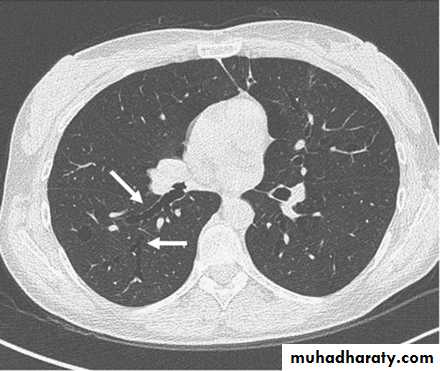

• Chest X-ray

• The presence emphysema can be suspected on routine chest radiography but this is not a sensitive technique for diagnosis.

• Large volume lungs with

• a narrow mediastinum and

• flat diaphragms are the typical appearances. In addition, the presence of bullae and irregular distribution of the lung vasculature may be present.

• In more advanced disease, the presence of pulmonary hypertension may be suspected by the prominence of hilar vasculature. The chest X-ray is not a very good indicator of the severity of disease and will not be able to identify patients with COPD without significant emphysema.

• However, the chest X-ray is useful to look for complications during acute exacerbations and to exclude other pathology such as lung cancer.